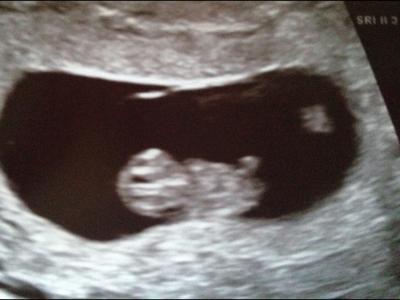

Eigentlich wollten sie mich noch da behalten aber ich wollte Heim zu meiner Familie! Darf hier beruhigt Paracetamol und Vomex nehmen ohne Angst haben zu müssen dass es schadet!Habe auch ein Bildchen bekommen mit 1 Füschen drauf;-) Hat hier noch jmd richtige Migräneattacken und weiß Tips? Massagen machen es nur schlimmer bei mir! Ich weiß dass es nur linksseitig bei mir ist wie als wäre dort ein entzündeterStrang oder so......

Bild zu Gestern Abend aus dem KH Heim - Forum für April - Mamis